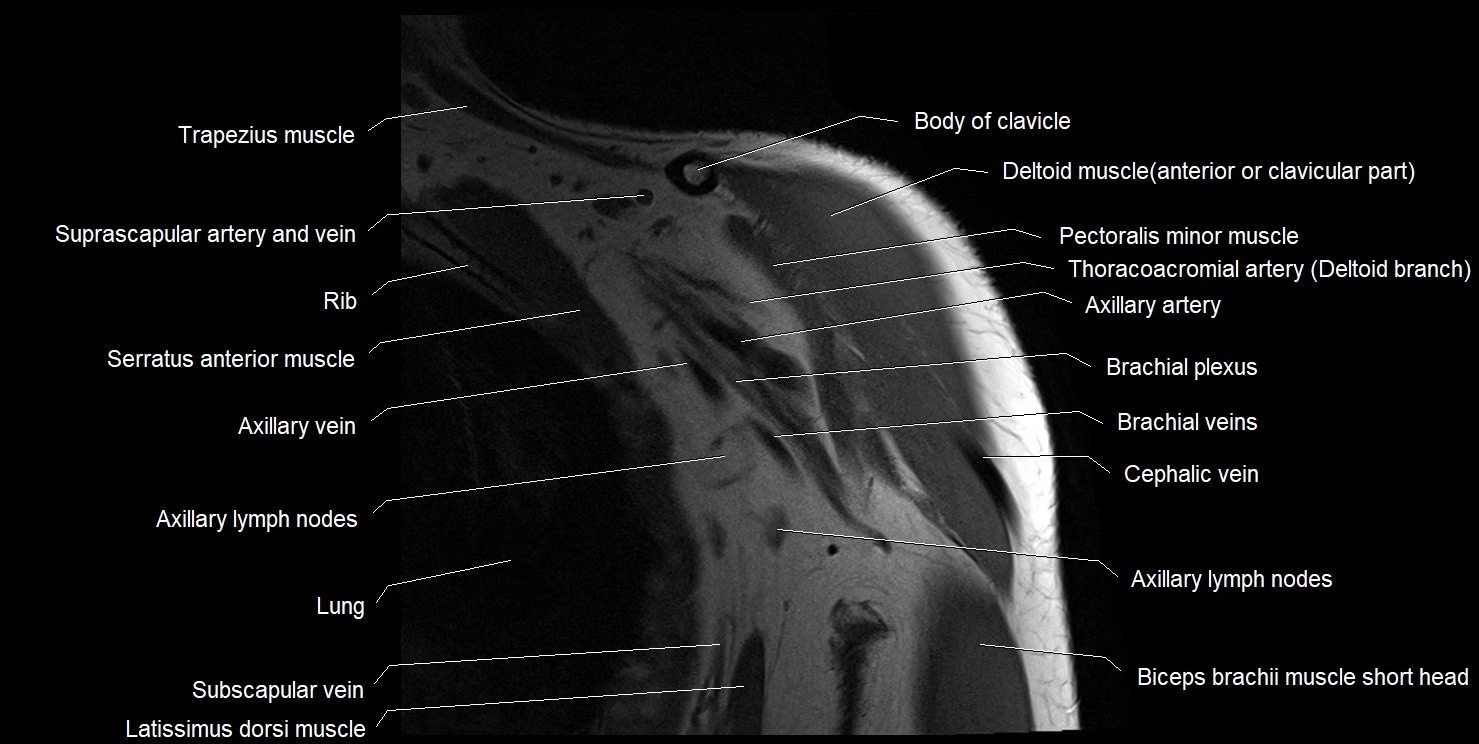

CT image

image